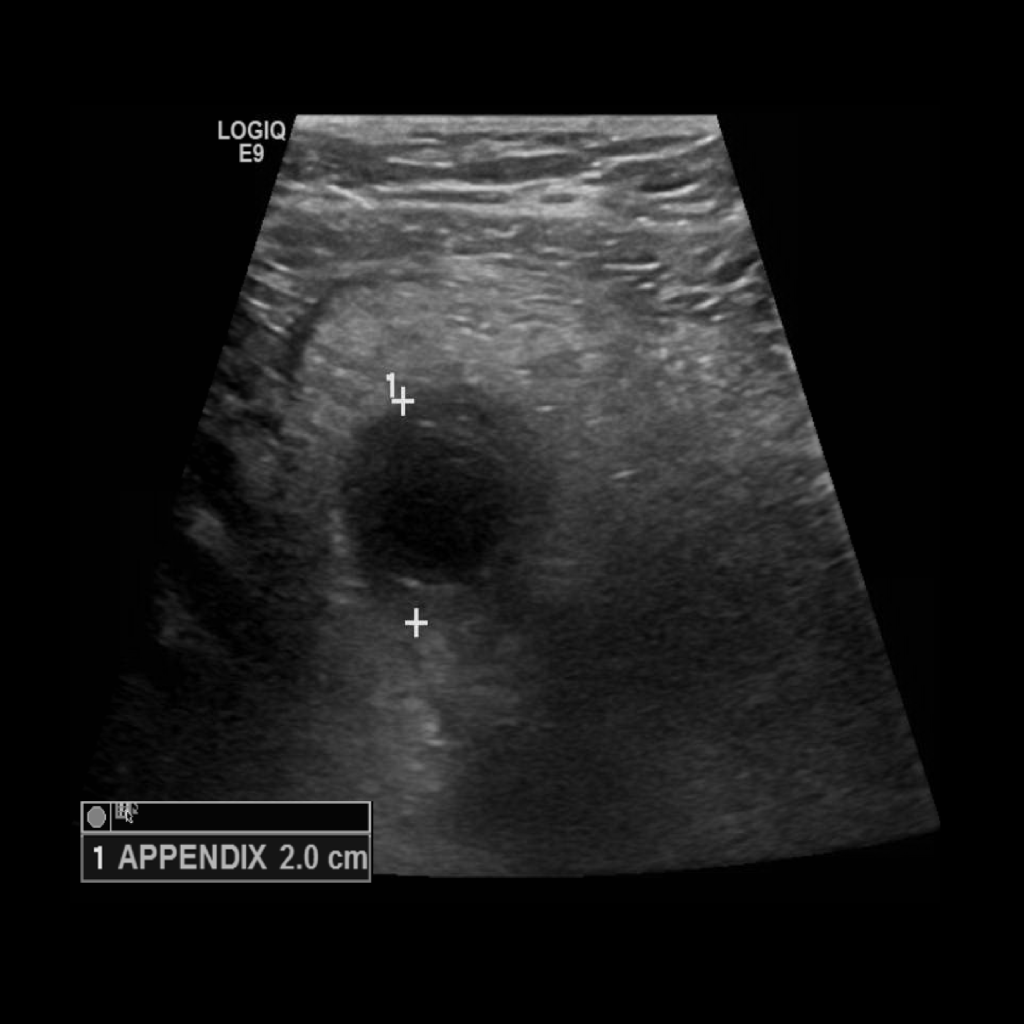

Appendicitis 1

2 cm appendix in an obese patient. Used the curvilinear probe to get better penetration.